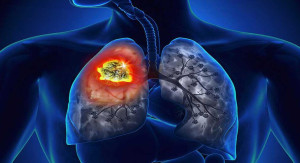

Theo thống kê của Bộ Y tế cho thấy, nước ta có gần 28.000 người lao động mắc bệnh bụi phổi, tuy nhiên con số thực tế có thể cao hơn gấp nhiều lần....